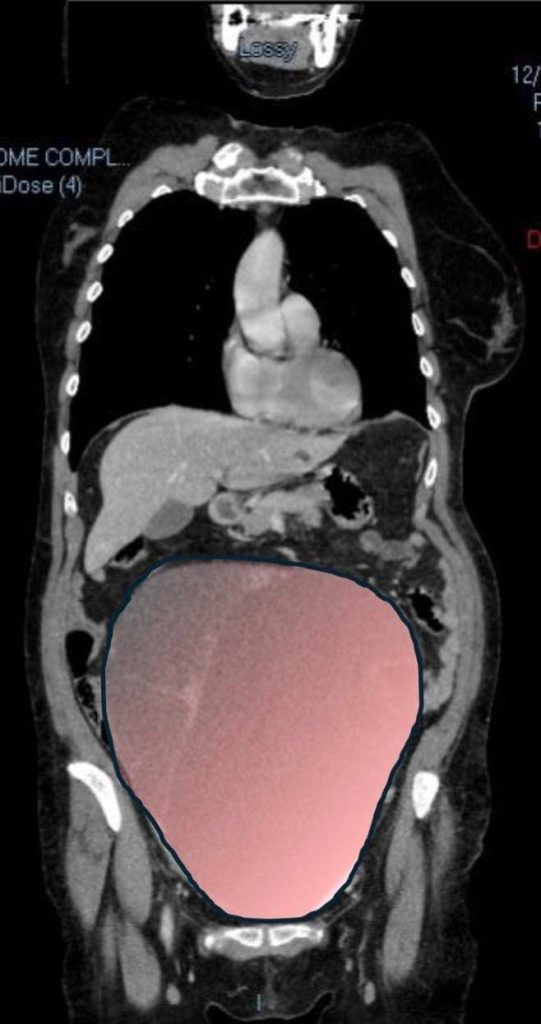

According to NeedToKnow, the surgical procedure lasted for about six hours. During the operation, doctors successfully removed a 28-centimeter tumor that weighed approximately 6 kilograms.

The City of Health and Science of Turin, where the surgery was carried out, described the tumor as being “comparable in volume to a full-term twin pregnancy.”